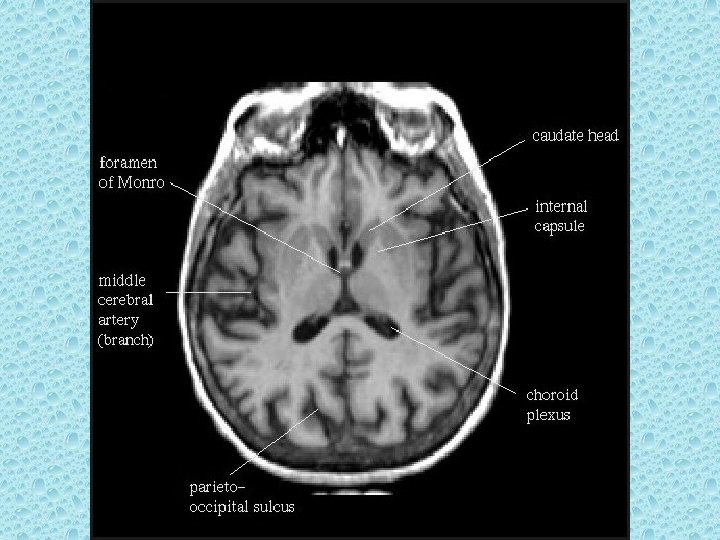

SEREBRAL PARANKİMDE BULUNAN YAPILAR • • Beyaz ve gri cevher Girus ve sulkuslar Lentiform nükleus: Putamen ve globus pallidus İnternal ve eksternal kapsül Talamus Kaudat nükleus ve korpus kallozum Ventriküller Koroid pleksus

VENTRİKÜLLER • Lateral ventriküller: frontal, oksipital ve temporal hornlar, korpus ve atrium • Foramen monro • 3. Ventrikül • Akuaduktus silvii • 4. Ventrikül • Foramen Lucka (çift) ve magendi (tek)

KAFA İÇİNİ BESLEYEN ARTERLER • Bilateral karotid sistem: İnternal karotid arter - A. oftalmika, a. kommunikans posterior, a. koroidea, a. serebri anterior ve media • Vertebrobaziler sistem: Vertebral arterler ve baziller arterlerden oluşur - A. Serebellaris posterior inferior (pica), anterior inferior (aica), a. serebellaris superior, a. serebri posterior